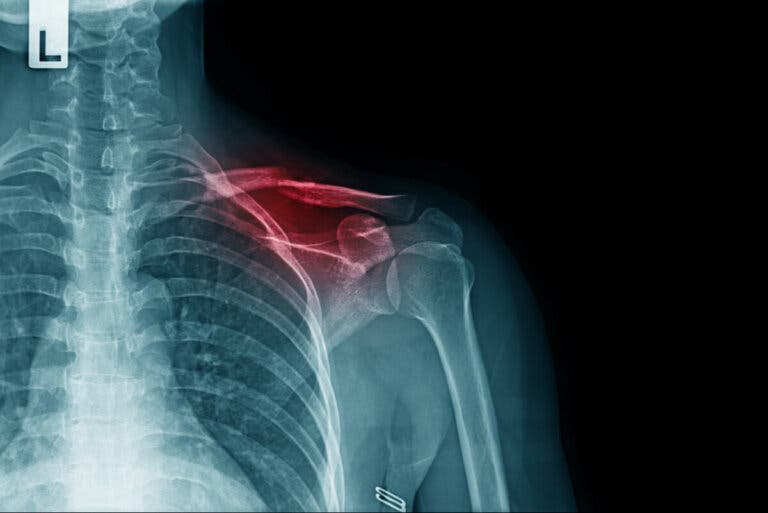

La prueba complementaria que más se utiliza para ayudar al diagnóstico es la radiografía. Con ella se puede observar la línea de fractura y la disposición de los huesos. Sin embargo, en algunos casos pueden ser necesarias otros estudios más específicos, como la tomografía computarizada.